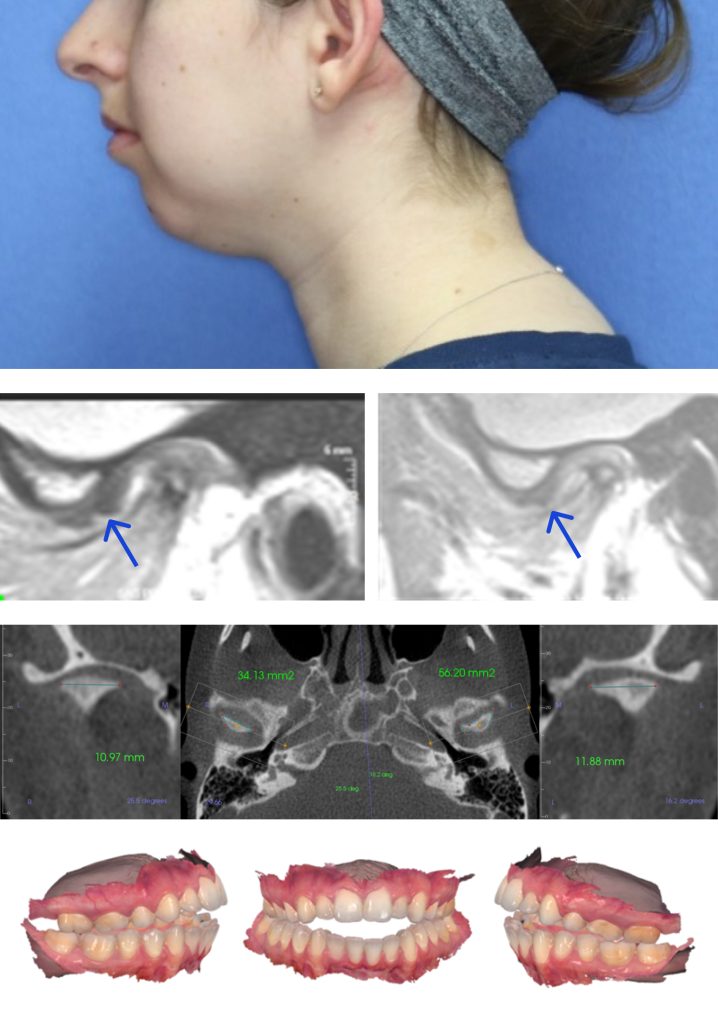

Idiopathic condylar resorption (ICR) has been discussed extensively1-8 since Burke9 introduced the term in 1961. In 2017, Young6 described ICR as “a condition with no known cause, which manifests as progressive malocclusion, esthetic changes, and often pain” (Figs. 1–4). The premise that ICR doesn’t have a known cause should be re-evaluated, however, given the insights that three-dimensional imaging with MRI and CBCT have provided over the past 40 years.

In 2019, Lei16 authored a study that used CBCT to evaluate the occurrence of degenerative TMJ changes in adolescents and young adults with recent onset disc displacement without reduction (DDw/oR).

This study acquired the CBCT and clinical data of 300 patients — 254 females and 46 males, with a mean age of 20.93 ± 4.77 years — who’d been diagnosed with unilateral DDw/oR within the past 12 months, based on the research diagnostic criteria for temporomandibular disorders. CBCT images of symptomatic and contralateral asymptomatic TMJs were independently evaluated and scored by two radiologists.

- Condylar OA changes were present in 59.3% of the joints with DDw/oR. Early-stage OA changes (loss of continuity of articular cortex and/or surface destruction) constituted most of the alterations.

- Prevalence of early-stage OA increased from 24% to about 60% one month after TMJ closed-lock occurred. Logistic regression analysis showed the risk of developing early-stage OA changes was 5.33 times higher one month after onset of DDw/oR.

- A high prevalence of degenerative TMJ changes was observed with recent-onset DDw/oR in adolescents and young adults. Early diagnosis and intervention of DDw/oR is therefore prudent.

Given the clear connection between disk displacement in growing patients and the lack of condylar growth and development, our views on ICR should be reevaluated. Idiopathic implies that the cause of the problem is unknown, but in this case, it’s clear that if the disk is not covering the condyle in the growing patient, there’s an increased risk the condyle won’t grow to its full genetic potential.

While the disk is usually discussed in terms of whether the TMJ hurts or locks, the more important role of the disk relates to mandibular and maxillary growth. The Guidelines for Assessment, Diagnosis and Management published by the American Academy of Orofacial Pain18 state that “MRI represents the current gold standard of diagnostic imaging for soft tissues,” which includes the TMJ disk.

If we don’t obtain MR imaging in the growing Class II patient, we assume there’s an “idiopathic” issue rather than a growth defect from a structural alteration in the TMJ. When we obtain MR imaging in the growing Class II patient, we’re better able to understand the problem and to offer realistic treatment options.